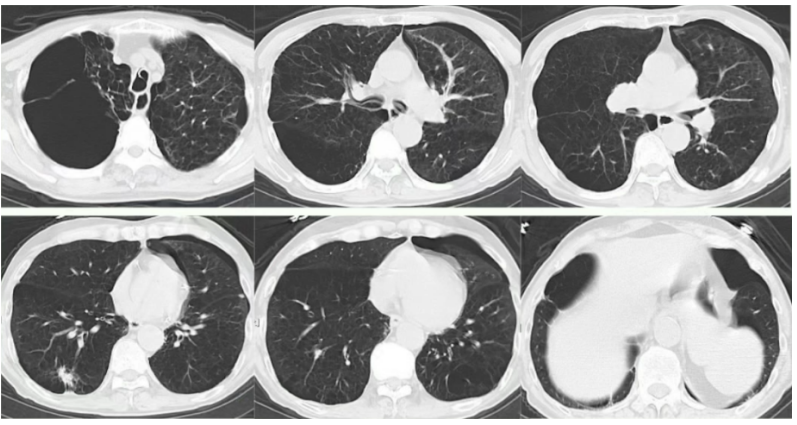

- 胸部CT:左侧气胸,肺气肿,肺大泡,两肺结节较前相仿(图1)。